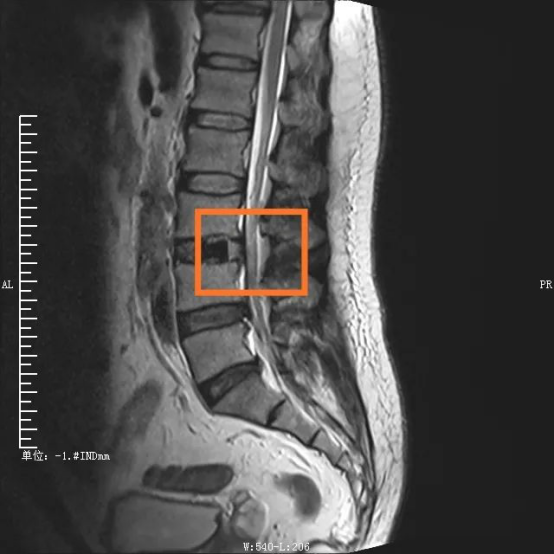

“如果说传统开放性腰椎手术走的是一条‘大刀阔斧’的路,那么OLIF则是走巧妙的创新之路。”主刀医生邓雷(重庆市医学会神经脊柱学组副组长)说道,患者陈先生被腰痛缠绕1年多,近段时间严重到走路都困难,经检查发现腰3/4椎间盘突出、腰椎管狭窄,属于典型的腰椎疾病。

手术部位术前/术后对比图

在外科医生眼中,衡量一台手术是否成功、是否属于微创范畴,术中的出血量、组织损伤、手术时间以及术后康复时间都是重要考量因素。传统腰椎手术从后方入路,需要切开分离肌肉组织,手术创伤大,时间长,出血量多。考虑到传统手术对患者肌肉等组织损伤较大,且手术费用及住院时间增加,脊柱脊髓专业组决定采取更安全高效的OLIF手术。

“OLIF手术采用侧方入路,手术区域在椎管前方,不破坏后方结构,不分离脊柱后方肌肉,极大地减少了组织损伤。”邓雷介绍,这种技术巧妙在于,充分了利用腹膜后主动脉与腰大肌前缘之间的自然间隙,到达目标椎体斜外侧,结合神经外科显微手术技术,切除病变椎间盘,实现椎间融合。若手术顺利,术中患者出血仅20ml左右,患者术后2天就能下床活动,3天即可出院。